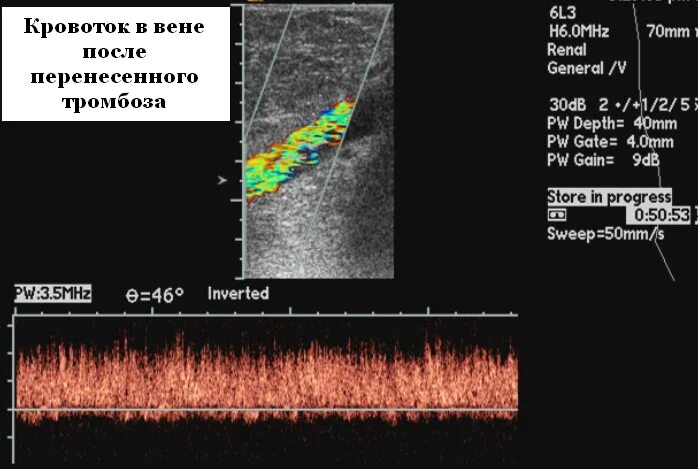

Как проверить сосуды на наличие тромбов